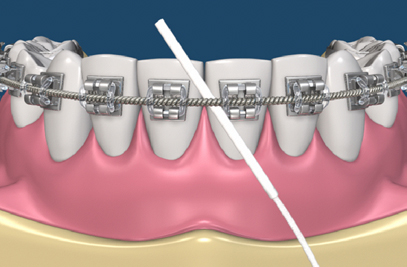

Braces vs Invisalign in Karachi: Which One Is Actually Worth Your Money?

Transform Your Smile with Reliance: Braces for Adults in Karachi

When you hear the word braces, you might capture teenagers with shiny metal smiles.

Getting That Confidence Smile: Orthodontics at Altamash Dental Clinic

You know that feeling when you see a picture of yourself and say, “If only my teeth were just a little straighter…” It happens more often than you realize.

Straight Talk: Uncover the Power of Orthodontics at Altamash Dental Clinic

Ever heard that braces are only for kids? Don't believe it. At 40 or 14, orthodontics can realign a healthier, straighter, and more confident smile. At Altamash Dental Clinic, our orthodontists provide cutting-edge braces treatment in Pakistan for crooked teeth, bite, and jaw alignment, which is both functional and visually pleasing. With state-of-the-art care [...]

Clear Path to Confidence: Invisalign Braces for Teens and Adults

Invisalign for Teens: Straightening Teeth with Confidence For teenagers looking for a hassle-free, confident path to straighter teeth, Invisalign provides a novel answer. With these almost undetectable aligners, teens may manage their daily lives without sacrificing their self-assurance. They offer a discrete alternative to traditional braces. With personalized, comfortable aligners, Invisalign not only straightens [...]

OrthodonticsTreatment: Your Smile Revolution

Your teeth alignment affects the overall structure of your mouth, and it also affects your oral health.

Veneers or Braces – What’s Best for You?

A wonderful smile can make a dramatic difference in your appearance, how you feel about yourself, and even what others think of you. If you want to improve your smile, two of the most popular cosmetic dental treatments are veneers and braces. While both correct issues like crooked teeth, gaps, or discoloration of teeth, they [...]

Everything You Need to Know About Orthodontics: Expert Care at Altamash Dental Clinic

A lovely smile leaves a lasting impact, but finding it usually surpasses mere physical appearance. Orthodontics, which is the specialty of dentistry concerned with straightening teeth and jaw relations, is all about enhancing your appearance as well as your overall oral health. In this blog, we'll discuss all that you should know about orthodontics, starting [...]